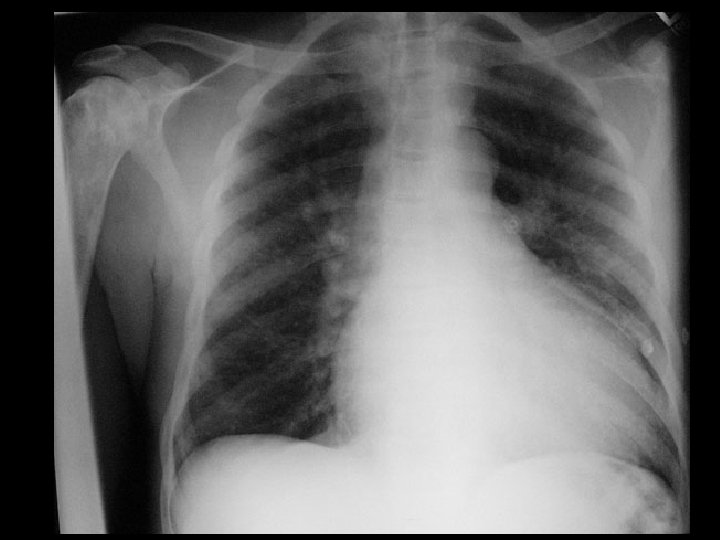

Cystic fibrosis • Findings: – hyperinflated lungs with diffuse, bilateral bronchiectasis • ddx: – immotile cilia syndrome – congenital immunodeficiency and recurrent infections